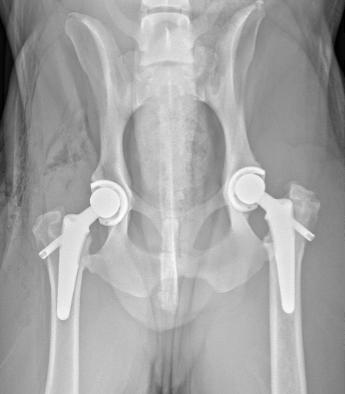

Hip: the first documented hip replacement in a dog was in 1957. Over the years, there have been numerous advances in the systems and implants we use. Commercially available cemented hip replacement became available in 1990. The first version of the cementless implants were introduced in 2003. There are now 2 main systems in place, both owned by Movera, Kyon and Biomedtrix.

Bridger Veterinary Specialists currently use the 3rd generation cementless implant from Biomedtrix called a lateral bolt in most patients.

1: Biomedtrix lateral bolt, cementless hip replacement